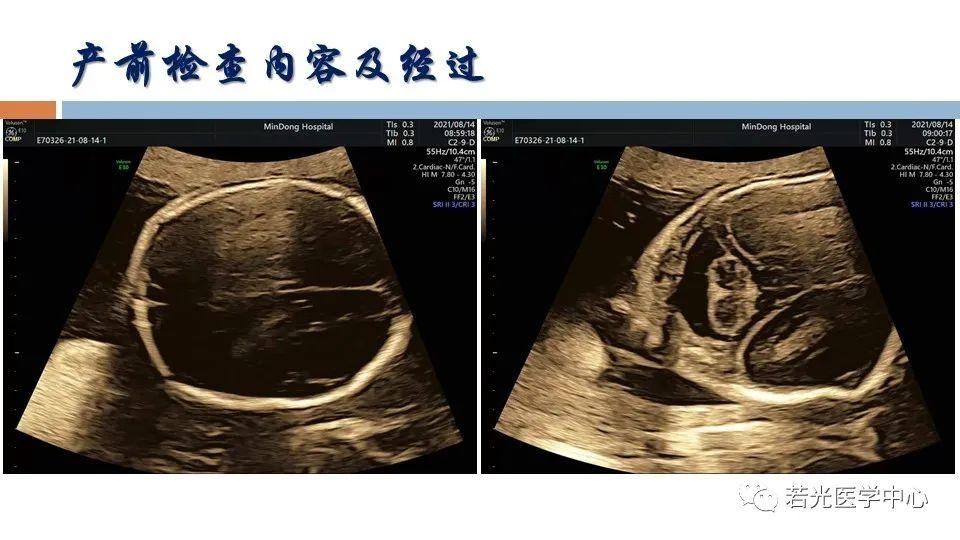

(6)表型-征象-分子遗传联合分析,遗传咨询分析与分子诊断。产前胎儿影像(超声,MRI)等异常,各类胎儿先天畸形与出生缺陷表型-基因-家系遗传分析,产前产后胎儿异常分析咨询,生育健康咨询。